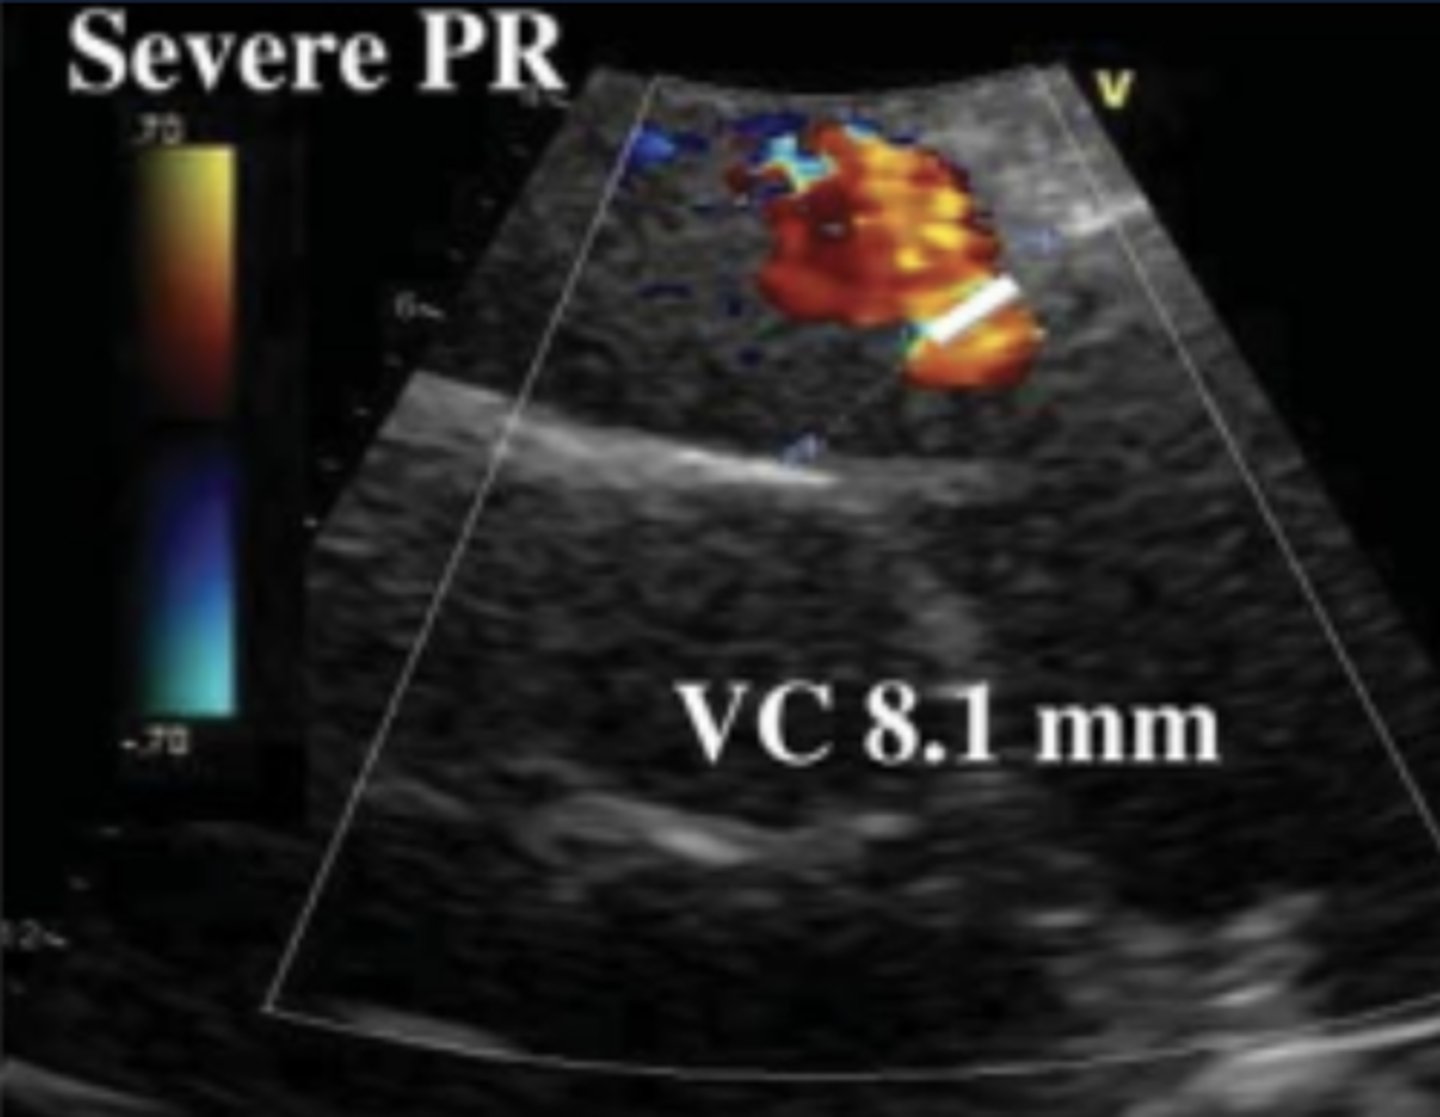

Vena Contracta for PR

Measure in PSAX

Must see flow convergence, neck, and PR jet

VCW to PV annulus diameter ratio for Severe PR

> 50%